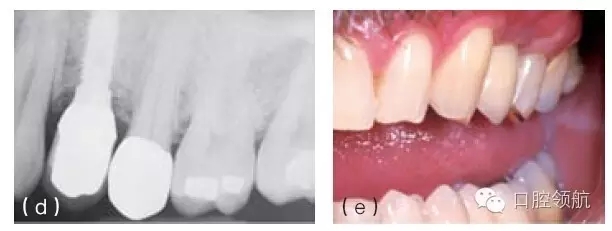

圖10.1 (a)個性化基臺連接在種植體上的牙合面觀。螺絲的長軸對應的是種植體的長軸,螺絲的長軸傾斜,基臺螺絲孔通頰側(cè)面。(b)成品基臺的頰面觀,螺絲的入口清晰可見。(c)上頜種植體的轉(zhuǎn)移替代體,反映種植體頰側(cè)傾斜的角度。(d)使用個性化鑄造基臺能獲得良好的美學效果。(e)轉(zhuǎn)移替代體顯示種植體的方向不平衡。(f)轉(zhuǎn)移替代體在口內(nèi)頜面觀,如圖可見遠中種植體舌傾。(g)制作診斷蠟型以確定最終修復體的外形。(h)個性化基臺的代型,遠中種植體的螺絲入口位于近中舌側(cè)位。固定局部義齒將會粘結(jié)于個性化基臺上。

圖10.2 (a)治療前缺牙區(qū)的切面觀,可見唇側(cè)有骨缺損。(b)缺牙區(qū)植骨后的切面觀,可見唇側(cè)牙槽嵴厚度增加。(c)治療前X線片顯示上頜第一前磨牙的拔牙區(qū)有較大骨缺損。(d)植骨后植入種植體。(e)由于種植體植入前對骨缺損區(qū)進行植骨,第一前磨牙的冠在高度和頰側(cè)面的位置都接近正常。

圖10.4 (a)在頜骨模型上,環(huán)鉆置于種植體上。環(huán)鉆是空心柱狀的,鉆的末端有切割螺紋。它放在種植體上,可以順著種植體邊緣周的骨組織的切線方向環(huán)行去除骨組織,從而使種植體移除造成的創(chuàng)傷減到最小。(b)種植單冠的頰面觀,種植修復后患者產(chǎn)生持續(xù)性的疼痛,且無法緩解,需要取出種植體。(c)根尖片顯示種植體正常。(d) 取出牙冠,翻瓣暴

露種植體。(e)用環(huán)形鉆取出包繞種植體的骨環(huán)。(f)環(huán)形鉆包繞種植體,環(huán)形切削達種植體全長。(g)環(huán)形鉆切削完畢,(環(huán)形鉆中心的)切除的骨組織包繞種植體,種植體周圍已被分離,只有根尖區(qū)還有骨組織與種植體相連接。將使用一種器械,置于骨環(huán)周,切斷根尖區(qū)的骨組織。(h)包含種植體在內(nèi)的骨環(huán)被取出。(i)取出后置于外科盤上,可見種植體及附著周圍薄層的骨組織。種植體植入時曾植骨,種植體周可見殘留的顆粒狀的骨移植材料。(j)種植體移除后,去骨創(chuàng)面的牙合面觀。(k)將骨移植材料(同種異體骨與異種骨移植材料混合)放置在去骨創(chuàng)面中。(l)放上屏障膜,用釘固定。